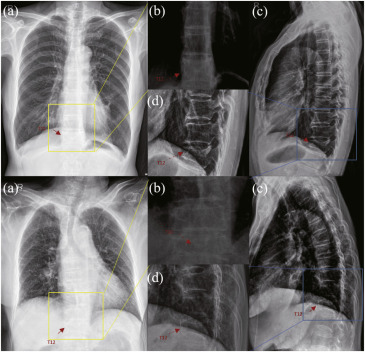

图1. 准确识别椎体压缩性骨折的主要挑战。图1展示了两种异常骨折(轻度/重度)病变区域及其在不同模态中相邻正常椎体的比较。(a)、(b)分别是胸部正位X光片及其放大视图;(c)、(d)分别是胸部侧位X光片及其放大视图。箭头指示T12椎体的病变区域。